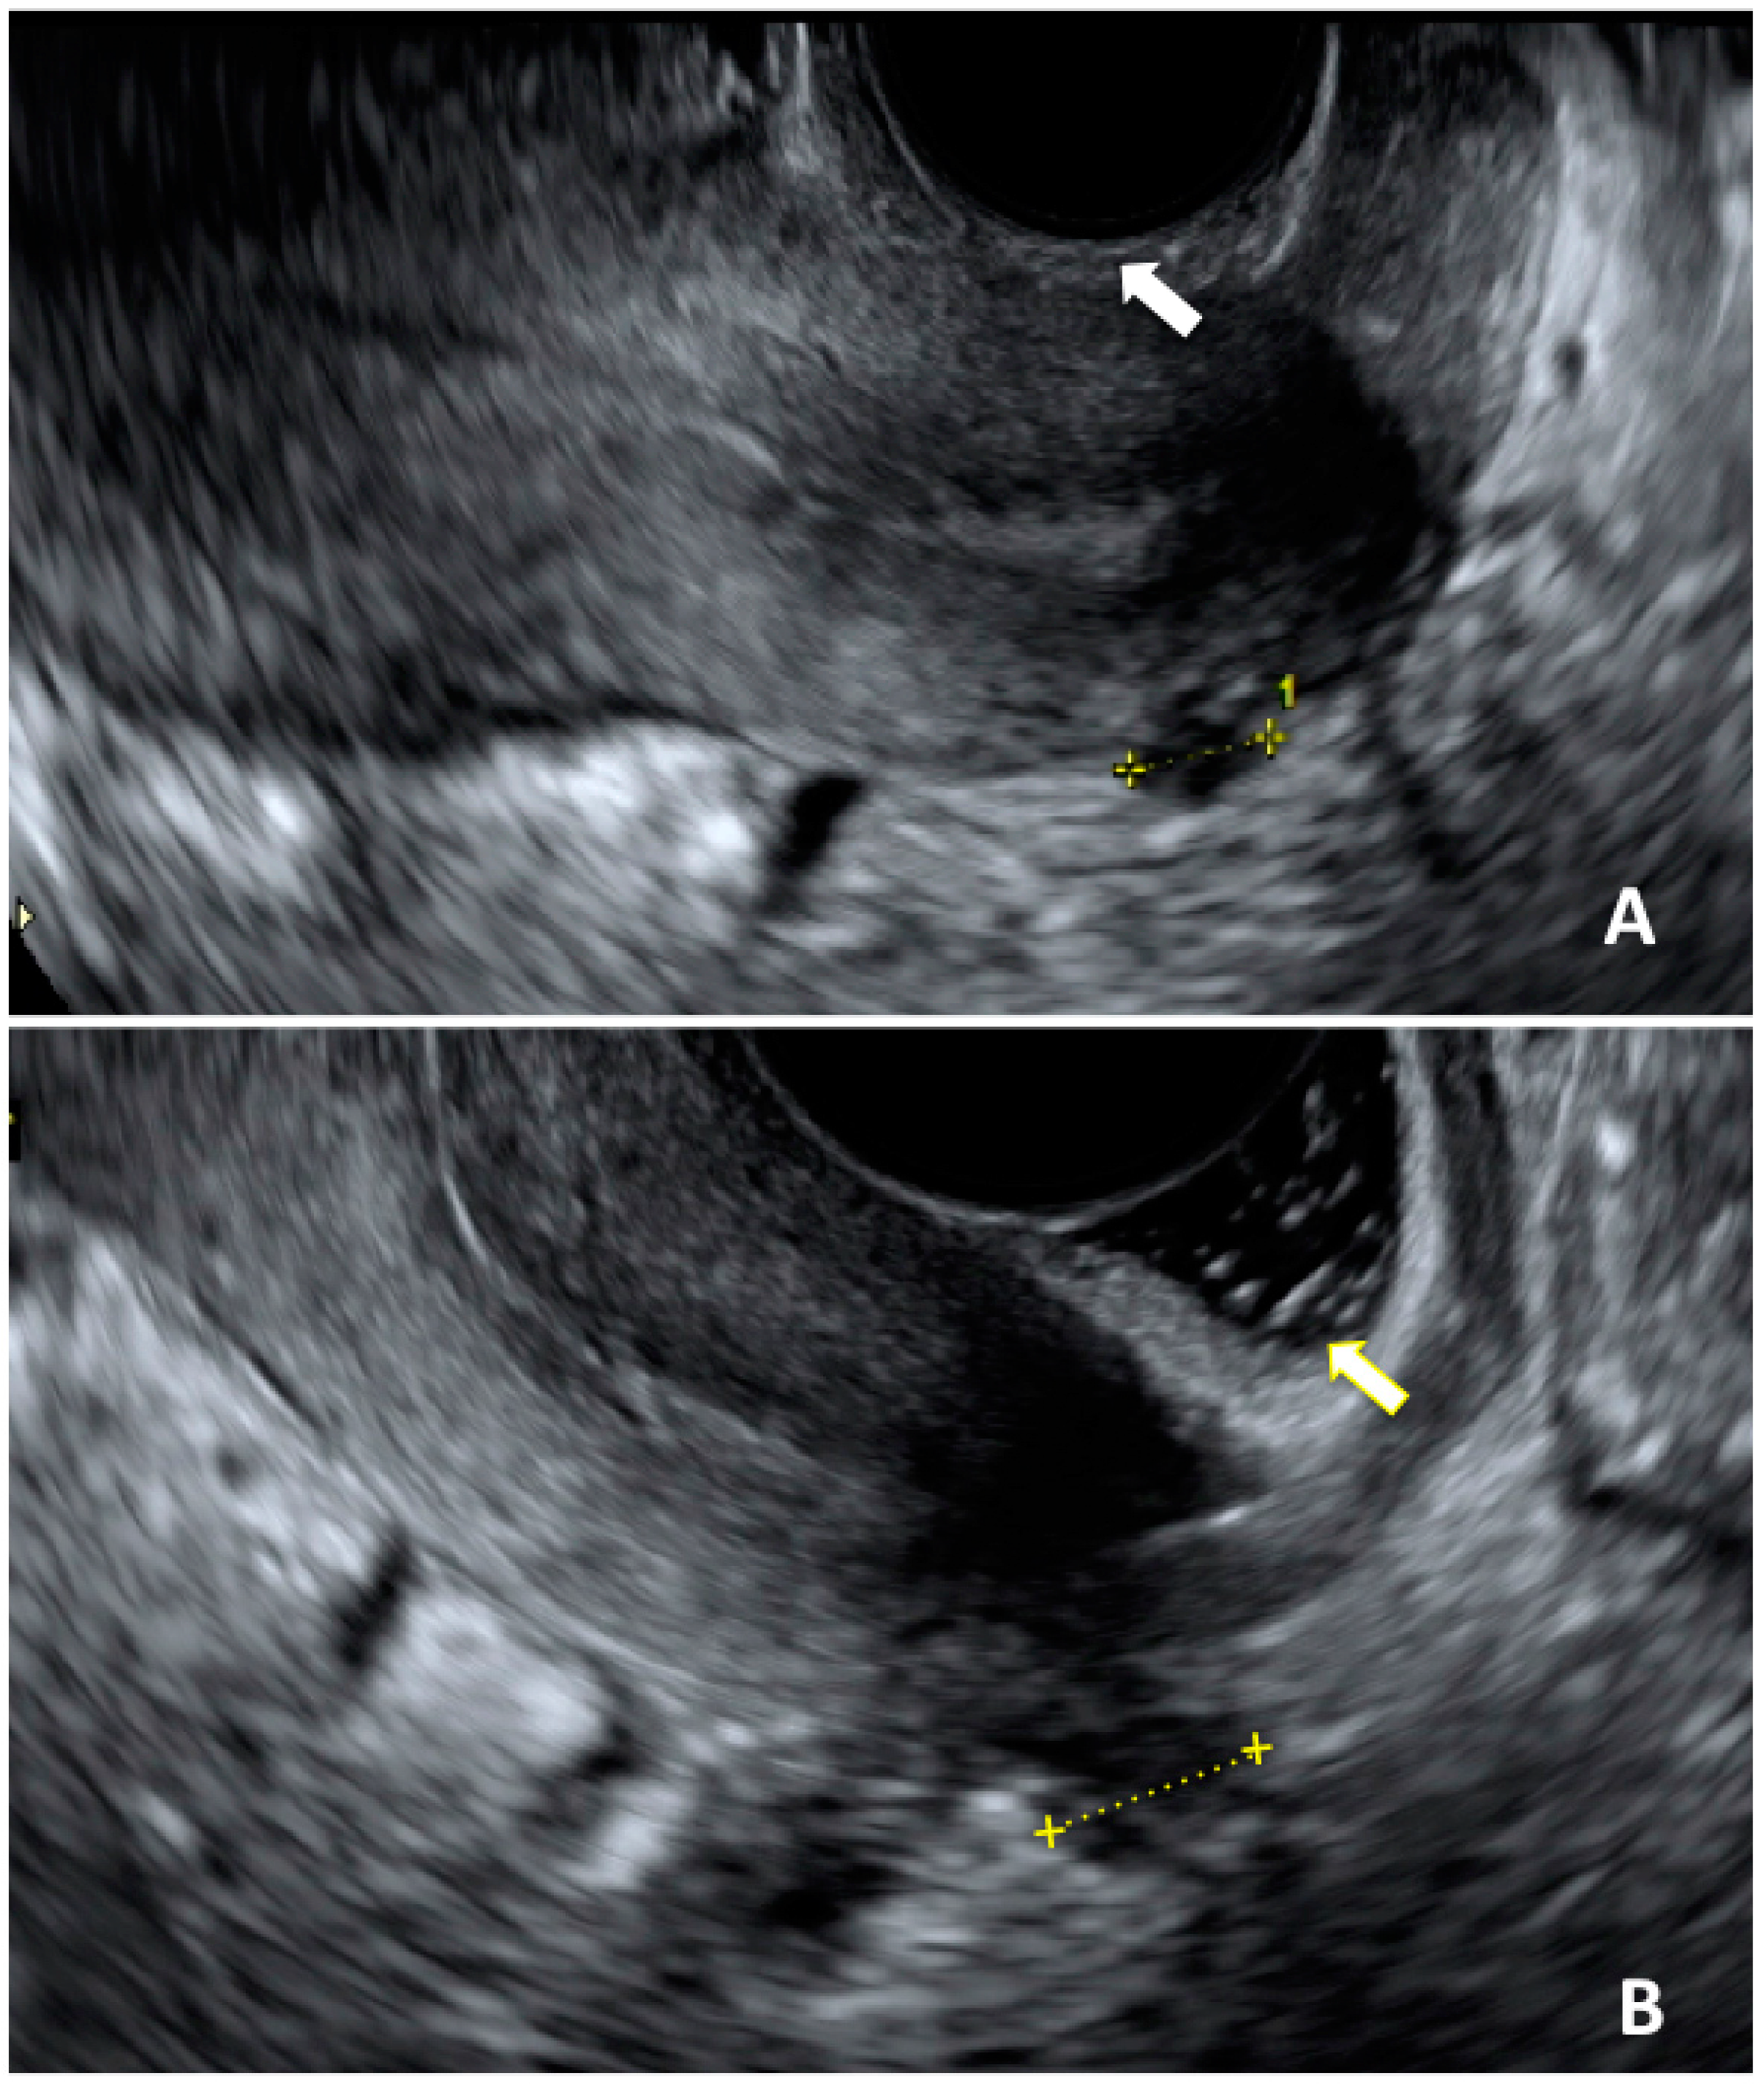

- Martire, F.G.; Lazzeri, L.; Conway, F.; Siciliano, T.; Pietropolli, A.; Piccione, E.; Solima, E.; Centini, G.; Zupi, E.; Exacoustos, C. Adolescence and endometriosis: Symptoms, ultrasound signs and early diagnosis. Fertil. Steril. 2020, 114, 1049–1057. [Google Scholar] [CrossRef]

- Martire, F.G.; Russo, C.; Selntigia, A.; Nocita, E.; Soreca, G.; Lazzeri, L.; Zupi, E.; Exacoustos, C. Early noninvasive diagnosis of endometriosis: Dysmenorrhea and specific ultrasound findings are important indicators in young women. Fertil. Steril. 2023, 119, 455–464. [Google Scholar] [CrossRef]

- Güdücü, N.; Sidar, G.; Işçi, H.; Yiǧiter, A.B.; Dünder, I. The Utility of Transrectal Ultrasound in Adolescents When Transabdominal or Transvaginal Ultrasound Is Not Feasible. J. Pediatr. Adolesc. Gynecol. 2013, 26, 265–268. [Google Scholar] [CrossRef]

- Ohba, T.; Mizutani, H.; Maeda, T.; Matsuura, K.; Okamura, H. Evaluation of endometriosis in uterosacral ligaments by transrectal ultrasonography. Hum. Reprod. 1996, 11, 2014–2017. [Google Scholar] [CrossRef] [PubMed]

- Koga, K.; Osuga, Y.; Yano, T.; Momoeda, M.; Yoshino, O.; Hirota, Y.; Kugu, K.; Nishii, O.; Tsutsumi, O.; Taketani, Y. Characteristic images of deeply infiltrating rectosigmoid endometriosis on transvaginal and transrectal ultrasonography. Hum. Reprod. 2003, 18, 1328–1333. [Google Scholar] [CrossRef] [PubMed]

- Alborzi, S.; Rasekhi, A.; Shomali, Z.; Madadi, G.; Alborzi, M.; Kazemi, M.; Nohandani, A.H. Diagnostic accuracy of magnetic resonance imaging, transvaginal, and transrectal ultrasonography in deep infiltrating endometriosis. Medicine 2018, 97, e9536. [Google Scholar] [CrossRef]